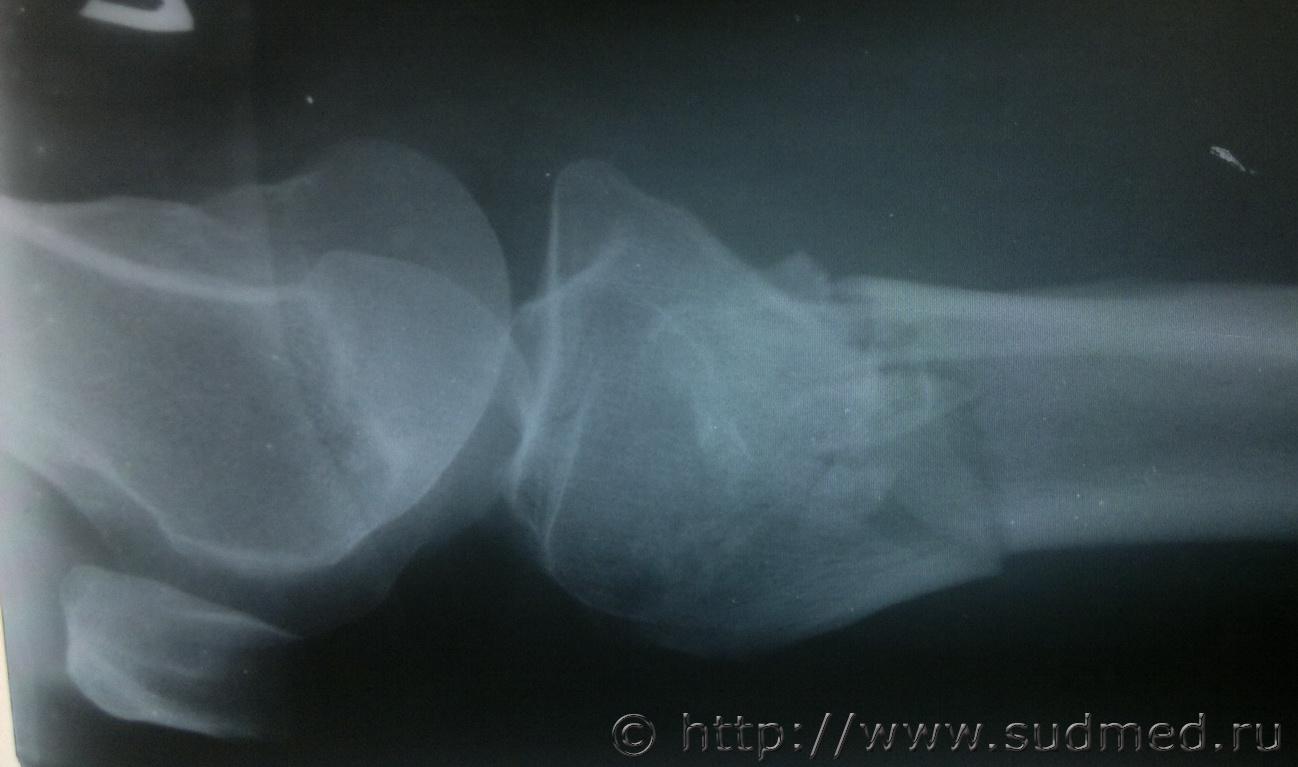

Женщину, 70 лет сбил автомобиль, после чего она была доставлена в ОКБ где были сделаны рентгеновские снимки, которые прилагаю, достаточно ли будет снимков для определения степени вреда здоровью, так как точный диагноз из истории болезни не удалось узнать.Судебная медицина - Прикрепленное изображение Судебная медицина - Прикрепленное изображениеСудебная медицина - Прикрепленное изображениеСудебная медицина - Прикрепленное изображениеСудебная медицина - Прикрепленное изображение

достаточно. Единственное, что по снимку непонятно - открытый или закрытый перелом? В украине это имеет существенное значение для определения степени тяжести, если Вы из России - коллеги точнее скажут, но судя по локализации здесб вроде будут тяжкие телесные

тяжкий вред.

Большое спасибо за быстрый ответ, закрытый перелом обеих ног.